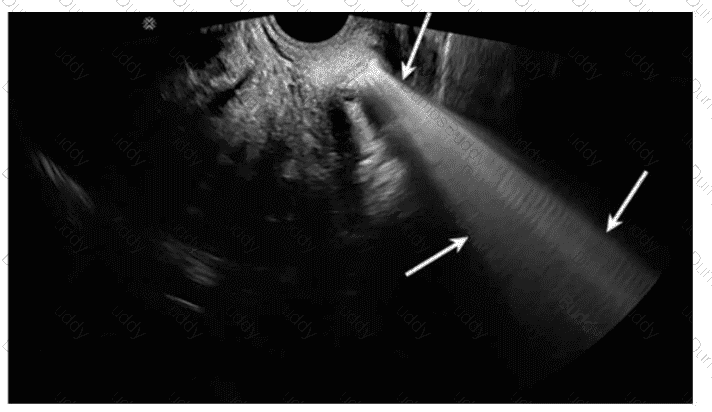

Questions 31

In this image, which artifact is demonstrated?

SPI Question 31

Options:

A.

Mirroring

B.

Aliasing

C.

Range ambiguity

D.

Spectral broadening

Buy Now